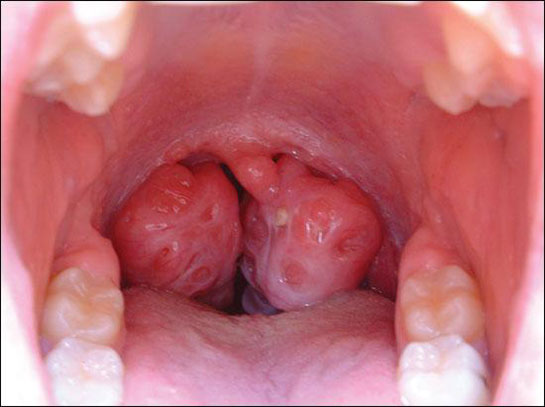

Bademcik Ameliyatı Ne Zaman Yapılmalı?

Bademcik Şişmesi Belirtileri ve Tedavisi

Bademcik Büyümesi Belirtileri ve Tedavisi

Kriptik Tonsillit Belirtileri ve Tedavisi

Bademcik Belirtileri ve Tedavisi